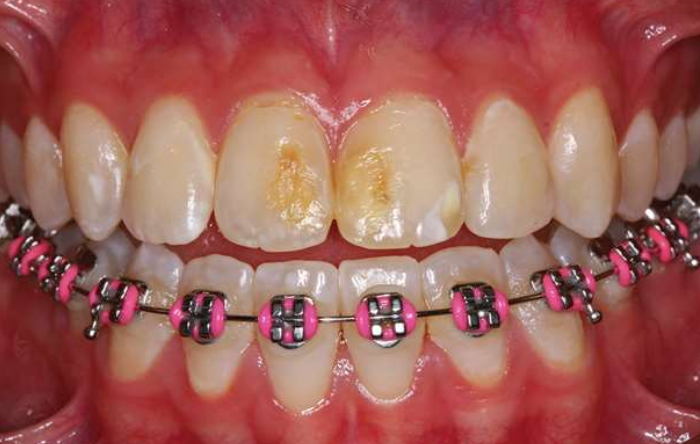

Xerostomia (dry mouth,口乾症) | - | 舌乳頭萎縮、鵝口瘡(oral candidiasis), 蛀牙 ![]() |

Sjogren syndrome | 慢性、系統性、自體免疫疾病 | 腮腺 (85%) | 中年 |

乾眼症檢測: Schimer test

把試紙放在病人眼下5分鐘,觀測溼透的程度是否低於8mm

Value(試紙沾濕長度) | Condition |

---|---|

>10mm/5min | Normal |

<5mm/5min | Highly suggestive |

0-2mm/5min | Strongly confirm a dry-eye state |

乾口的檢測